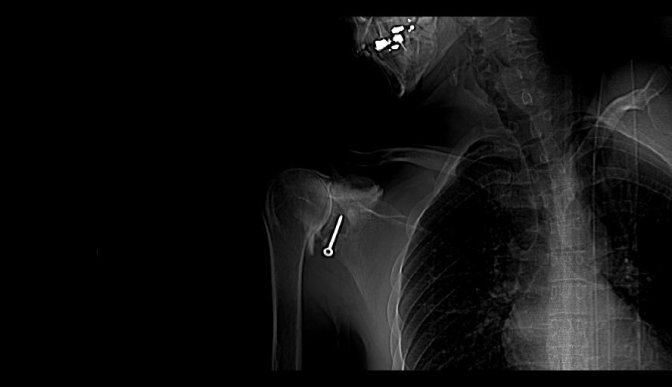

J’ ai dû me faire opérer, oh pas de grand chose, une luxation d’ épaule mais le chirurgien s’ est complètement planté, j’ étais dans un sale état quand enfin j’ ai rencontré un médecin disposé à m’ aider, on me l’ avait bien caché, il a cependant dû me réopérer trois fois.

J’ ai tenté de porter plainte contre l’ hôpital, il parait que ça ne se fait pas, ça m’ a coûté des nerfs et pas mal d’ argent pour des rapports qui informent que la greffe était mal positionné, qu’ elle ne pouvait pas prendre mais que l’ on ne peut cependant pas considérer qu’ il s’ agit d’ une erreur. De quoi s’ agit t’ il alors ? D’ une expérience ? Est ce que j’ ai servi de cobaye ? Je n’ en saurai jamais plus, le dernier expert m’ a conseillé d’ abandonner, que j’ allais me noyer dans cette affaire.